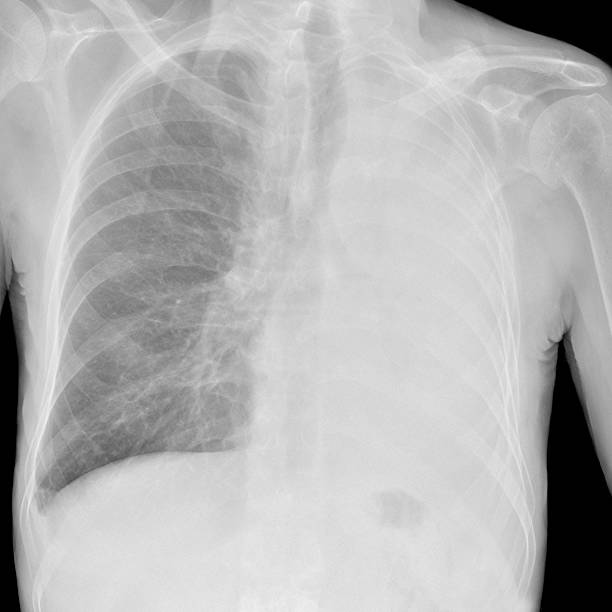

기흉(pneumothorax)은 폐와 흉부벽 사이에 공기가 쌓이는 상태를 말합니다. 이는 폐가 공기로 가득 차면서 폐가 축소되고 압축되어 발생합니다. 이러한 압축으로 인해 폐의 기능이 저하되며 호흡 곤란, 가슴 통증 등의 증상을 유발할 수 있습니다.

흉부 X선 검사

기흉이 의심되는 환자에게는 흉부 X선 검사를 실시하여 기흉이 있는지 확인할 수 있습니다. 이 방법은 비교적 쉽고 빠르게 기흉을 진단할 수 있습니다.